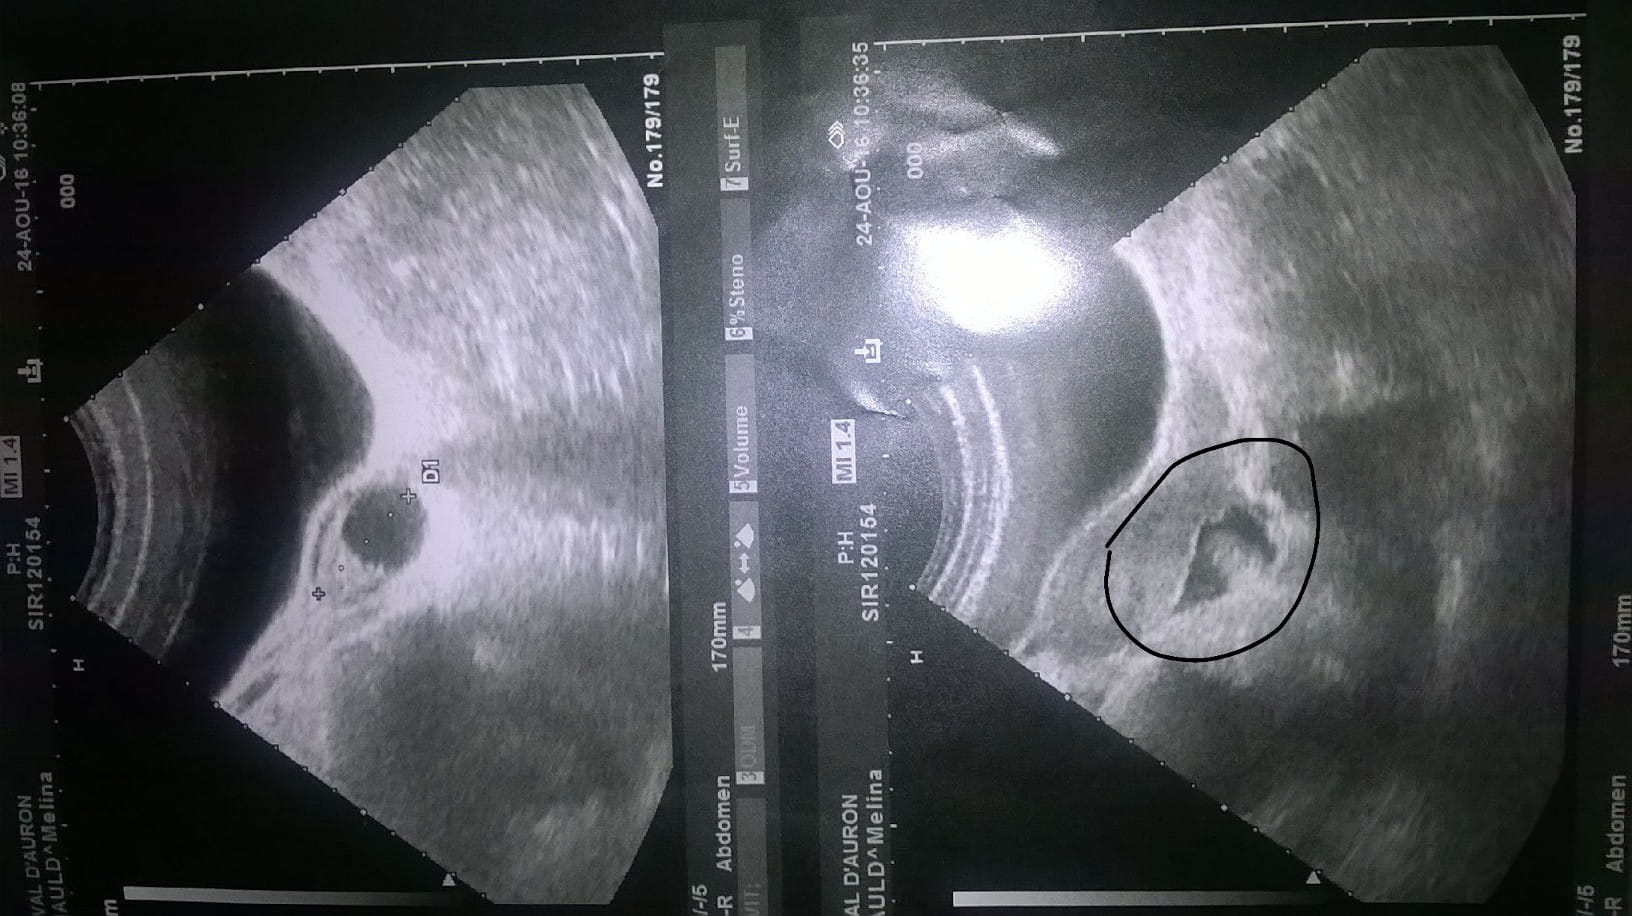

Je vous met la photo de mon échographie :

Je vais essayer de faire court ! Voilà depuis juillet que mon soucis dure. Tous le mois de juillet j'ai eu des symptômes de grossesse : du moins ce que mon médecin m'a dit (nausées, fatigue, bouffée de chaleur, vertiges, seins tendus, envie fréquente d'uriner...) mais celui qui dure depuis sont les douleurs aux ovaires (depuis les autres symptômes sont partis sauf vertiges et ovaires). Test de grossesse Négatif, donc mon médecin en a conclut à une infection urinaire mais malgré les médocs les douleurs aux ovaires persistent. J'ai eu mes rrrrr le 27 juillet mais pas comme d'habitude (4 jours seulement, sans douleurs, pas abondants et sur la fin couleur un peu rosé). Donc j'ai du aller faire une échographie abdominal, il m'a dit qu'il y avait une anomalie avec du liquide derrière l'ovaire donc il m'a envoyé aux urgences pour examens complémentaire. J'ai eu une échographie vaginal, et donc elle m'a dit qu'il n'y avait aucun soucis (utérus vide, ovaires tout à fait normal). Donc deux échographie et deux avis différents. Tous mon demandé (médecins, gynéco) si j'avais fais prise de sang Bêta HCG (deux et négatif).